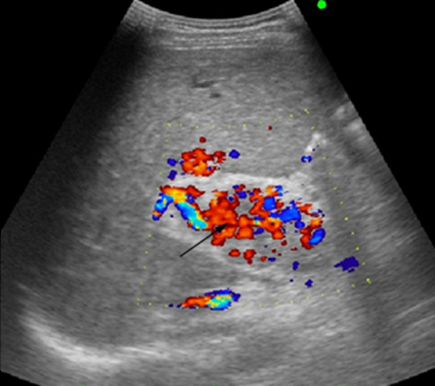

УЗ-картина кавернозной трансформации воротной вены – «портальной каверномы»

• Режим ЦДК